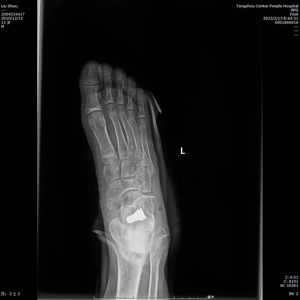

術中C型臂透視見:制動器位置良好,模擬左足負重試驗,患者足弓恢復良好。整個手術時間短,創傷小,見效快,僅用時30分鐘,微創刀口1cm,出血量不足5ml。術后左足石膏固定,2天后出院。?

(術后X線)